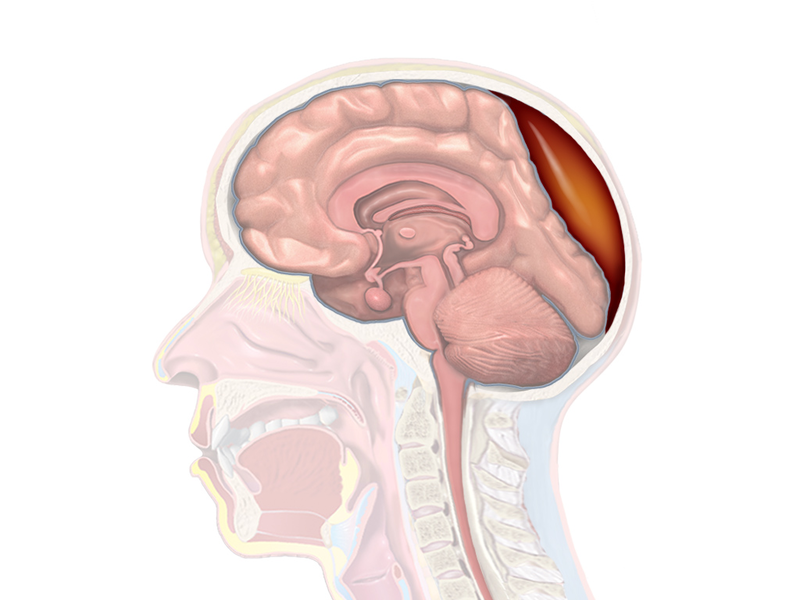

Uncal herniation is another type of herniation, in which the temporal lobe uncus is displaced under the tentorium cerebelli.

In an uncal herniation, compression of cranial nerve III, the oculomotor nerve, causes the ipsilateral eye to move “down and out” and the pupil to dilate.